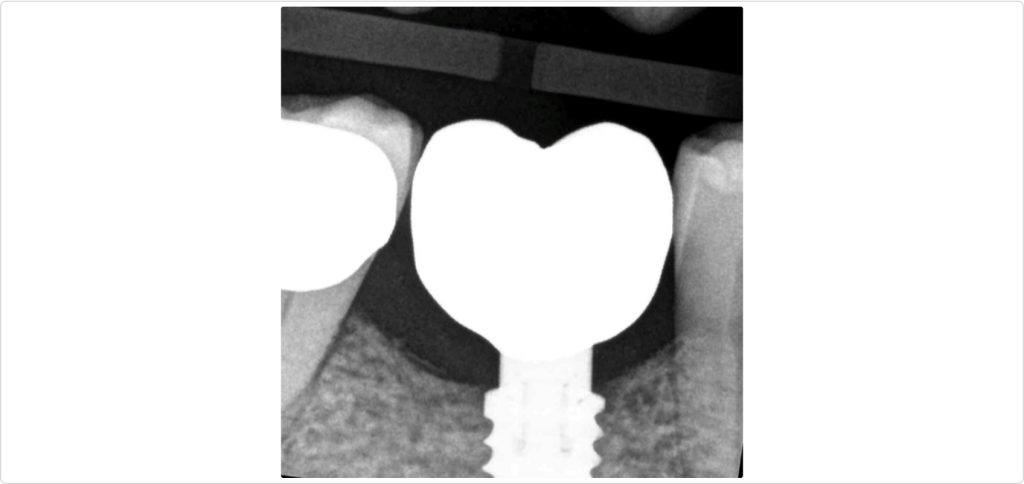

A radiograph taken six months after the procedure (Fig. 7) showed satisfactory healing and bone integration around the implant, indicating successful osseointegration and stability of the grafted site. Clinically, a lateral view of the ridge (Fig. 8) revealed minimal keratinized tissue at the site, highlighting the need for further soft tissue management.

A radiograph taken one year after crown delivery (Fig. 13) demonstrated stable marginal bone levels around the implant, confirming the success of the comprehensive surgical approach and the stability of the peri-implant tissues. This radiographic evidence was corroborated by clinical observations, which showed no signs of inflammation or mucosal dehiscence around the implant site. The stability of the bone levels indicated successful osseointegration, a critical factor for the long-term durability and functionality of the implant.